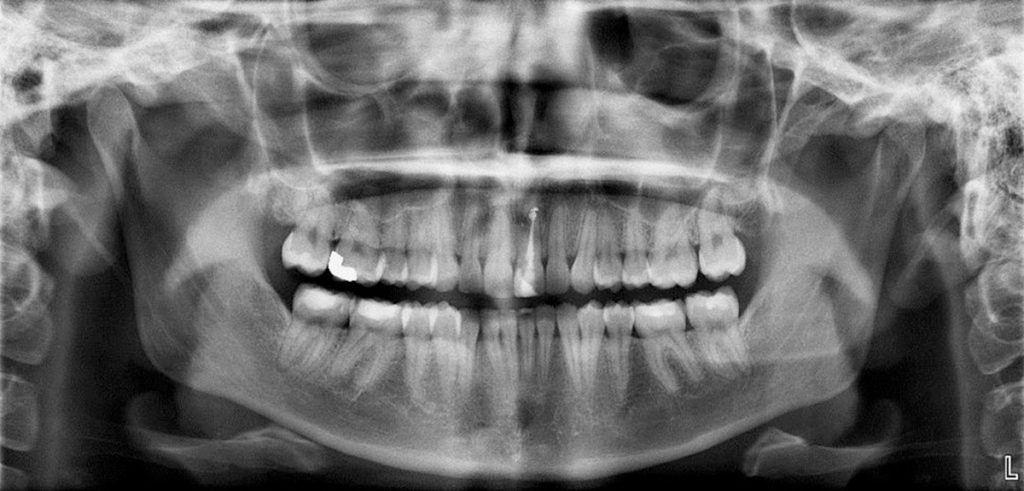

How Is CBCT Different from a Regular Dental X-Ray?

Traditional dental X-rays in Pune, such as OPG or intraoral X-rays, provide 2D images. While they are useful for basic diagnosis, they have limitations.

A CBCT scan, on the other hand:

• Offers 3D visualization

• Detects hidden issues not visible in 2D X-rays

• Improves treatment accuracy and safety

• Reduces surgical risks

That’s why CBCT has become essential for advanced dental procedures.